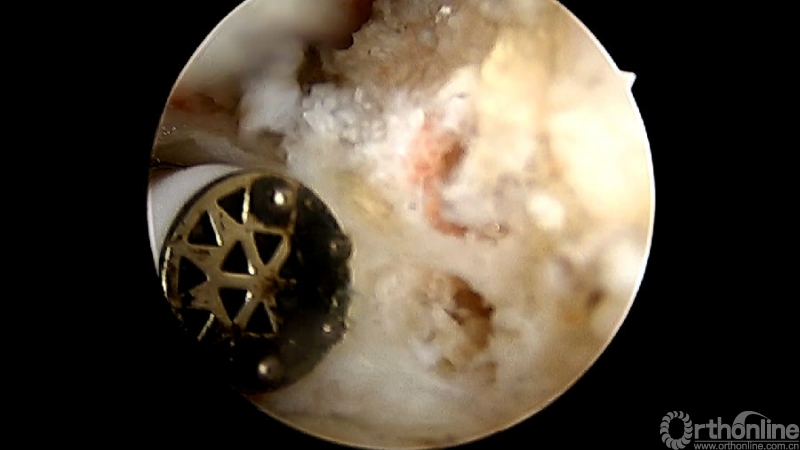

使用磨钻按照范围将下关节突内缘磨薄,然后用骨凿切除下关节突内缘显露出上关节突内缘及关节面。

术中切除下关节突内缘的范围